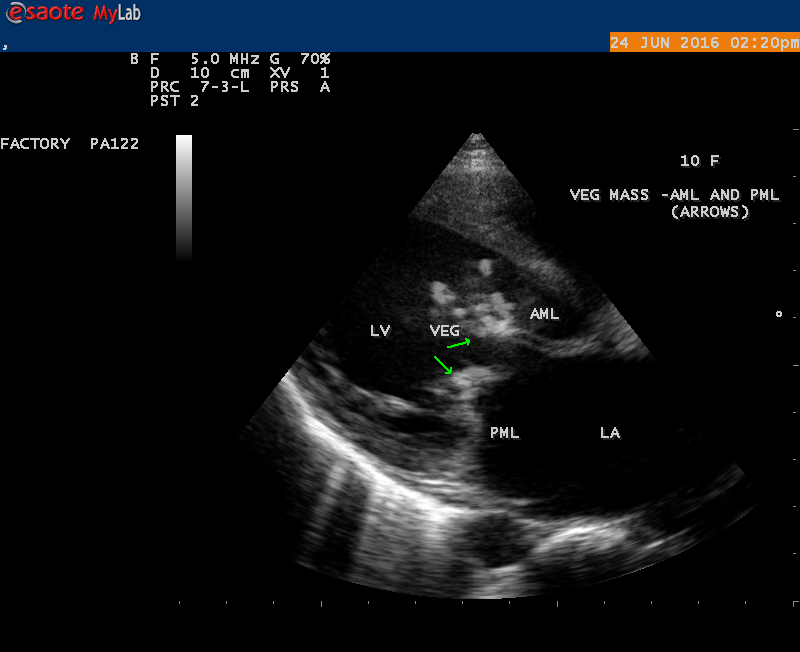

A 10 year female child was referred for echocardiographic evaluation with an apical systolic murmur. The child was having recurrent episodes of rheumatic fever (febrile illness with joint pains) at the age of 5-6 years and taken some treatment from the local medical practitioner, but she was not taken penicillin prophylaxis earlier. The child was remained afebrile for long period and no precipitating factors of infective endocarditis such as dental or genitourinary procedures in the past. General examination revealed normal growth and development, no cyanosis and clubbing and peripheral signs of infective endocarditis such s Osler’s nodes, Janeway lesions, Roths spots and splinter haemorrhages are not present and they are relatively rare in children. Physical examination revealed a grade 3/6 , blowing, high pitched, holosystolic murmur with a constant intensity and duration on dynamic auscultation and loudest at the apex with a radiation to left axilla and transmitted to the left infrascapular area and vertebral coloumn and it is due to the flow generating the murmur is directed posterolaterally within the left atrial cavity, suggesting the murmur of mitral regurgitation due to the rupture of chordae tendineae of anterior mitral leaflet. Blood culture revealed normal. Blood chemistry revealed the positive serum ASO titer, suggesting a recent streptococcal infection and other parameters are normal. X- ray chest reveled moderate cardiomegaly and ECG revealed a left ventricular volume overload pattern of eccentric hypertrophy due to LV dilatation as a result of severe mitral regurgitation and a normal rhythm. Transthoracic echocardiography revealed a giant vegetation ‘popcorn’ like in Figures 1,3 and 4 and ‘cucumber’ like in Figure 2, mainly attached to base and apical portion of anterior mitral leaflet as shown in Figure 31 and manifested in various size and shapes as shown in Figures 1 to 33. A flail anterior leaflet with a disorganized mitral regurgitation jet as shown in Figure 16 and 21 and the posterior leaflet is embedded with vegetation and resulting in ‘kissing forms’ as shown in Figures 13, 14 and 15 in echocardiography imaging. Tricuspid valve is also thickened and calcified as shown in Figure 2 in addition to thickened and calcified mitral leaflets, suggesting an underlying rheumatic etiology predisposing to the formation of vegetation. The child was given 1.2 million units of intramuscular benzathine penicillin injection as a therapeutic and initial prophylaxis dose for rheumatic fever and advised every 3 weeks for life long. Small doses of digoxin and diuretics are also prescribed and advised early surgery (mitral valve replacement) Transthoracic 2D images are as in Figures 1 to 33 are given below

The most common and direct evidence of infective endocarditis is the vegetation and it begins as a microscopic focus of infection and gradually grows into a conspicuous mass. It is typically an irregularly shaped, highly mobile, echogenic mass attached to the free edge of a valve leaflet ( most commonly at the coaptation line) and tends to develop on the ‘upstream’ side of the valve leaflets ( ie, the ventricular side of aortic valve and the atrial side of mitral and tricuspid valves. They may be seesile or pedunculated, but usually has an oscillating or fluttering motion, a typical feature of most vegetations. Vegetation move with the leaflet in a more chaotic (‘oscillating’) manner and it may prolapse through the valve into the LV (left ventricle) as it opens as shown in Figures 3, 4 and 16 and into LA (left atrium) as it closing (Figure 5 and 6) . The mass of vegetation is typically homogeneous with echogenicity similar to that of the myocardium. The infectious process often alter the valvular structure and function. Extensive involvement of the leaflet may result in chordal rupture, leading to severe regurgitation as shown in Figure 21 . Direct and typical signs of RMCT (ruptured mitral chordate tendineae) were chain-flail or whiplash-like changes and had an incidence of 86.7%, causing severe regurgitation and mitral chordal rupture is the leading cause of flail mitral leaflet[30]. A large vegetation may obstruct the valve orifice as shown in Figure 1 and 2 , sometimes termed as “obstructive-type bacterial endocarditis” and producing a functional valve stenosis ( Ping-Pong mitral stenosis [31]) similar to left atrial myxoma as shown in Figure 29.

The size and shape of vegetation vary due to curling of vegetation. The size of vegetation in this child is 35.6 x 9.3 mm as in Figure 17 , 20 x 23.7 mm as in Figure 1 , 32.9 x 13.9 mm as in Figure 2 .

The shape of vegetation varies in this child as ‘popcorn’ like (Figures 1,3 and 4 ), rod-shaped (Figure ), basket shaped (Figure 7 )[33-Figure 13.3], ‘baby in hand’ appearance (Figure 18), ‘cucumber shaped (Figure 2 ) and a ‘bunch of plantain’appearance (Figure 33 ), ring shaped (Figure 19 }, bileaflet structure (Figure 9 )with bileaflet MR jet as shown in Figure 10 . and kissing forms (Figure 13 - parasternal long axis view, Figure 14 - apical four chamber view and Figure 15 - short axis view)